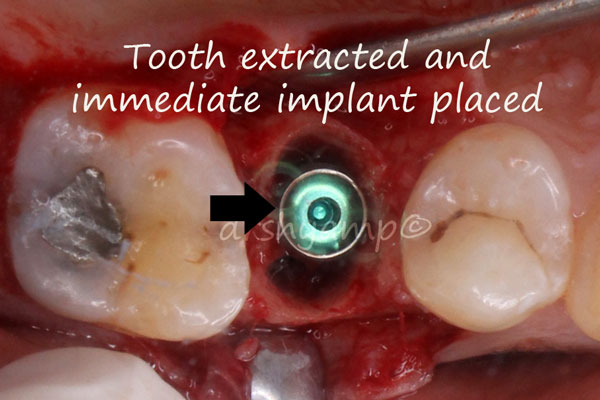

immediate dental implant

immediate dental implant

immediate dental implant

immediate dental implant

immediate dental implant

immediate dental implant

immediate dental implant

immediate dental implant

immediate dental implant